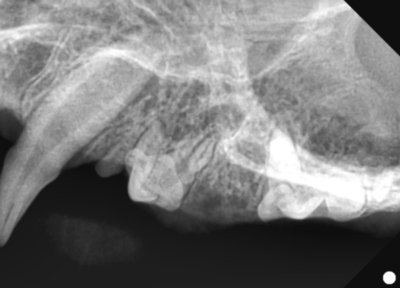

そして歯科レントゲン撮影を行いました。

右上顎も同様に中央に回転して生えている過剰歯があります。

左下顎は中央に重なって生えている過剰歯があります。レントゲンで確認しても、乳歯ではなく永久歯と考えられました。これらは過剰歯と呼ばれ、通常より本数が多く歯が生えてきます。かみ合わせが悪くなり、また歯間が狭くなり歯垢がつき、歯周病になりやすいです。そのため、不必要と思われる歯を抜歯しました。また、歯肉の増殖している部分を一部切り取り病理検査用の検体とし、それ以外の部分はメスで切除し正常に近い歯肉の形状に近づけました。

抜歯後は必ずレントゲン写真で残根がないか確認しています。

左上顎

右上顎

右下顎